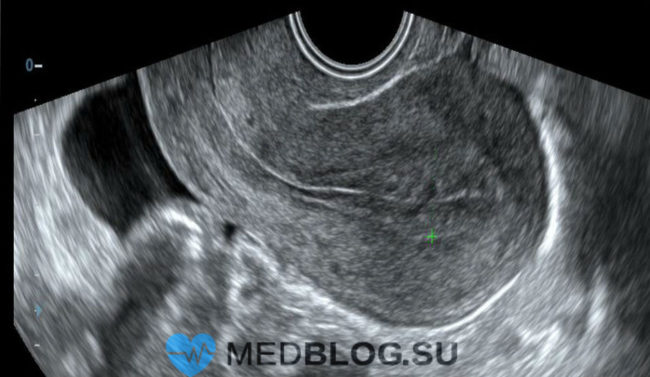

Рубцовая ткань на матке возникает на месте нормальной ткани после травмирования, инфекционного поражения или хирургического вмешательства, каковым часто является кесарево сечение. Как правило, эта ткань не такая упругая, что связано с низким уровнем коллагена в новообразовавшихся структурах. Рубцевание матки также известное как спайки, часто называют синдромом Ашермана. В зависимости от локализации и тяжести симптомов, рубцы…